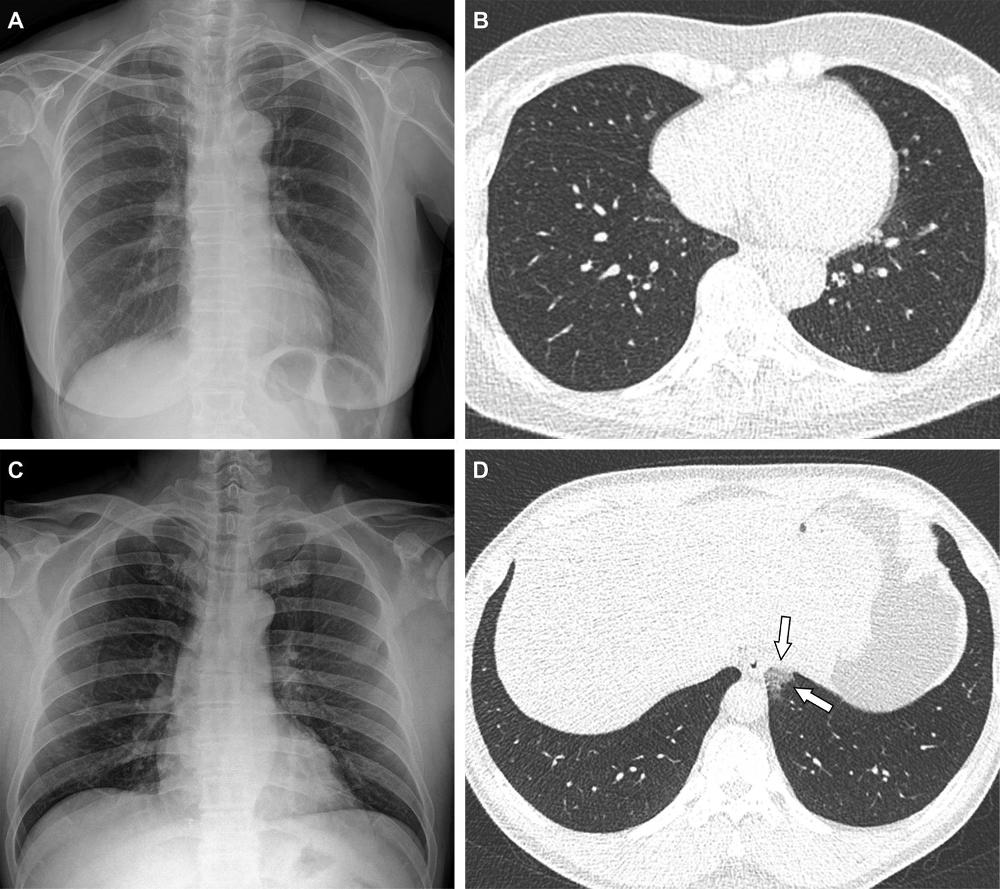

Figure 3. Representative cases showing pneumonia extents and patterns on chest X-ray (CXRs) and CT images. (E and F) A 36-year-old male with no history of vaccination for COVID- 19. The patient had no history of comorbidity. (E) CXR obtained at admission showing no abnormal opacification in either lung zone. CXR extent of pneumonia was scored as 0 (no evidence of pneumonia). (F) Axial chest CT image obtained on the same day showing unilateral ground-glass opacity with a nonrounded morphology and non-peripheral distribution in the left upper lobe (arrows). CT extent of pneumonia was scored as 1 (1-25% involvement) and this case was classified as indeterminate appearance of COVID-19 according to the RSNA chest CT classification system. (G and H) A 58-year-old male with no history of COVID-19 vaccination. The patient had a history of hypertension and diabetes. He required supplemental oxygen on admission and was admitted to intensive care unit one day later. (G) CXR at admission showing patchy ground-glass opacities in both middle- to lower-lung zones. CXR extent of pneumonia was scored as 2 (>25% involvement). (H) Axial chest CT image obtained on the same day showing multifocal ground-glass opacities with a crazy-paving appearance in bilateral lungs. CT extent of pneumonia was scored as 2 (>25% involvement) and was classified as typical appearance of COVID-19 according to the RSNA chest CT classification system.